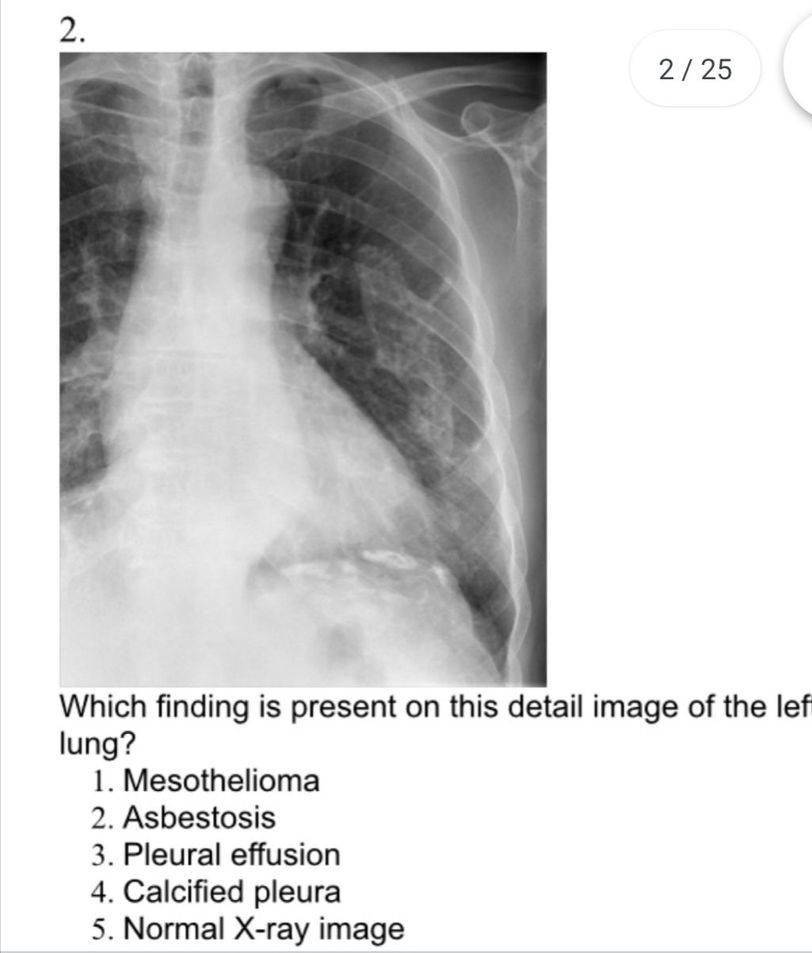

5.Normal x-ray.

4

3